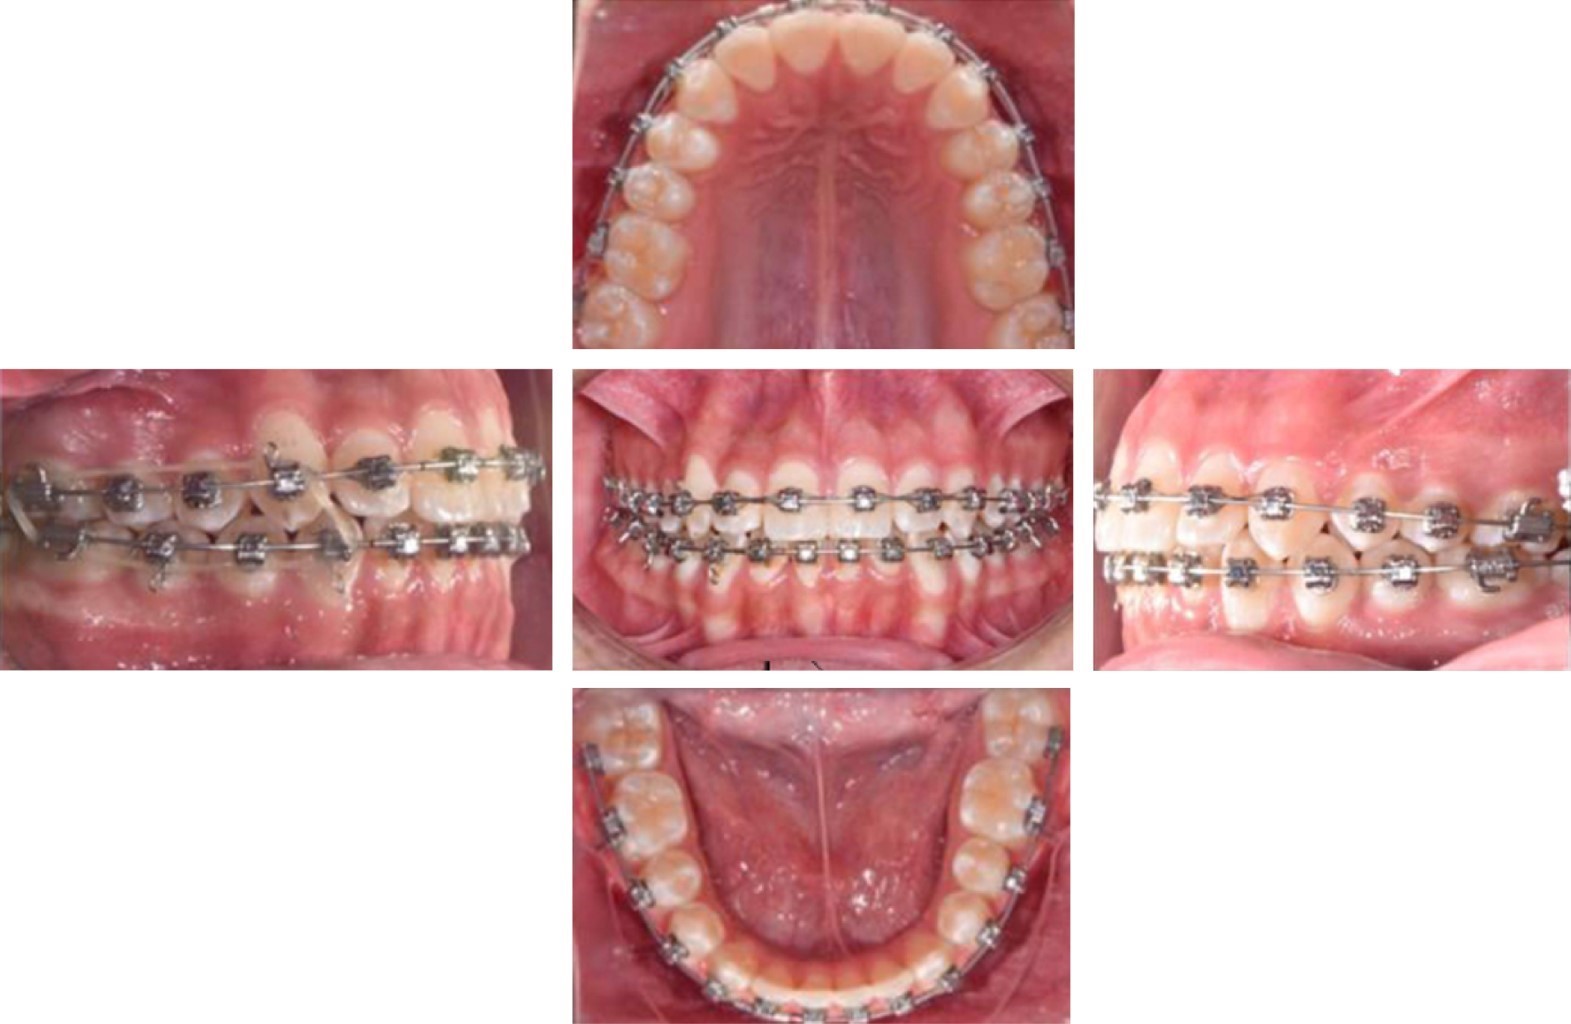

Paciente de género masculino de 13 años 10 meses de edad, sin antecedentes médicos relevantes, que acudió a la clínica de ortodoncia con motivo de consulta "quiero acomodar mi diente". En el análisis extraoral, el paciente presentó un perfil recto, biotipo dolicofacial incipiente, tercio inferior aumentado, pómulos sin proyección (Figura 1A). En la exploración intraoral el paciente mostró dentición permanente, clase II molar derecha, clase II canina derecha y clase I izquierda, forma de arco superior e inferior triangular, dientes grandes y cuadrados, línea media superior desviada 2 mm a la derecha, sobremordida horizontal 3 mm, sobremordida vertical 2 mm (Figura 1B). En el análisis de modelos en el estudio de Bolton presentó exceso maxilar de 3.2 mm, discrepancia de longitud de arco -6 mm superior y -2 mm inferior, con apiñamiento severo anterior superior (Figura 2).

Se inició el tratamiento colocando brackets de autoligado Damon® slot 0.022", con tubos superiores e inferiores en primeros y segundos molares, colocación de bite turbos posteriores y botones palatinos en órganos dentales 14, 15 y 16. Sin incluir el canino superior derecho al arco, se colocó un resorte de lateral a premolar derecho, el arco utilizado en la primera cita fue un CuNiTi 0.016" durante tres meses (Figura 4). Se continuó la alineación con un arco 0.018" CuNiTi superior y se comenzó el uso de elásticos tempranos ¼ 2.5 oz colocados de canino superior a canino y premolar inferior con un vector clase II.